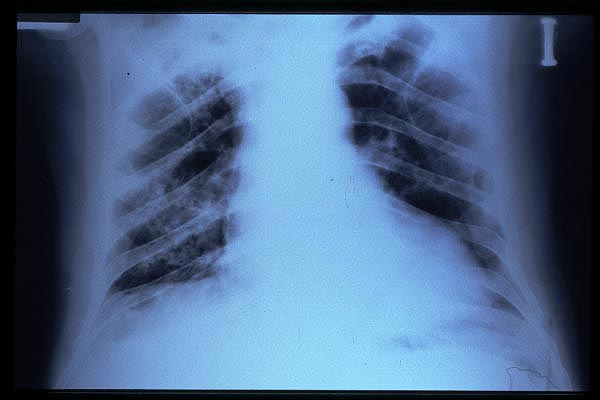

MO Distres respiratorio del adulto por trauma.